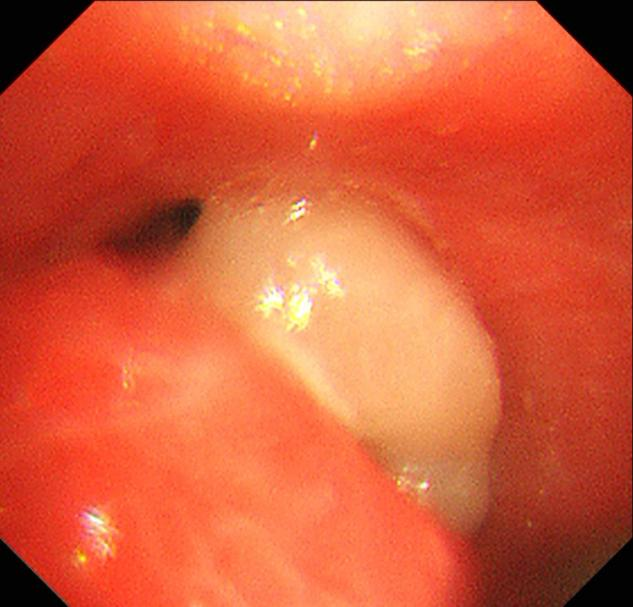

经过充分准备,呼吸与危重症医学科副主任医师詹峰为患者实施了经内镜气管内肿瘤切除术。术中,詹峰运用娴熟的内镜技术很快找到了病变,他发现患者隆突及右侧主支气管口被一新生物阻塞,气管阻塞率达90%以上。

术后患者气道内新生物被完全切除

詹峰当机立断,运用一次性高频电圈套器切除患者气道肿瘤,成功将气道内新生物完全切除。经过内镜复查,患者右侧各段支气管管腔已经恢复了通畅,而且术中出血量极少。手术极大地缓解了患者的病情,改善了她的症状,术后当天,患者咳嗽明显缓解,胸闷感也明显减轻。